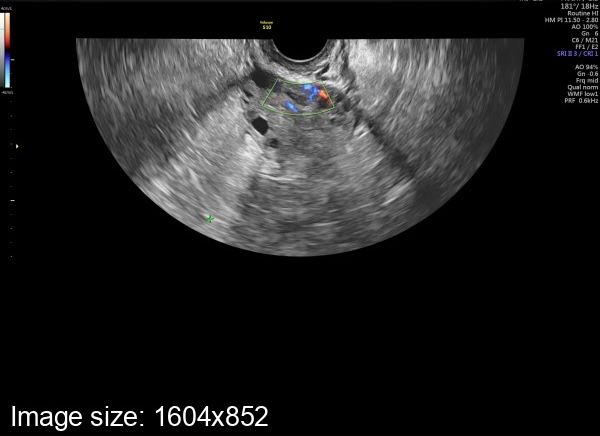

Пришла к врачу узисту , она говорит что овуляция была , но у меня раньше таких маленьких жт не было , кто разбирается подскажите

Визуально - Очень слабый кровоток в жт. Обычно вокруг жт яркое пламя. А размер жт не имеет принципиального значения.